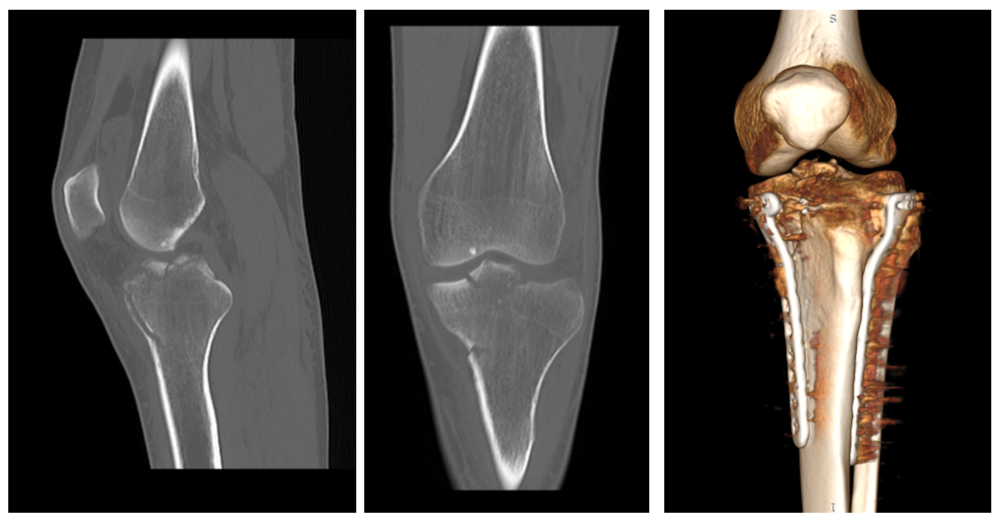

Молодой человек катается второй год, но травм раньше не получал. Он сделал обследования по рекомендации местных травматологов и в итоге решил обратиться на консультацию к специалисту Новосибирского НИИТО им. Я.Л. Цивьяна Минздрава России. По результатам дообследований был выявлен перелом проксимального отдела большеберцовой кости левой ноги с повреждением связочного аппарата, рекомендовано хирургическое лечение.

«Проведение хирургического вмешательства заняло около 3 часов. Операция проводилась под артроскопическим контролем. Мы выполнили репозицию перелома и в положении репозиции зафиксировали костные отломки специальными пластинами и винтами. Затем — рефиксация передней крестообразной связки: поскольку связка оторвалась вместе с костным фрагментом, необходимо было её повторно зафиксировать.

Для восстановления функциональности ноги пациенту нужно соблюдать ортопедический режим, носить тутор в течение 3 недель и передвигаться при помощи костылей до 2 месяцев», — комментирует заведующий травматолого-ортопедическим отделением №4 Александр Алекперов, проводивший операцию.

До и после операции